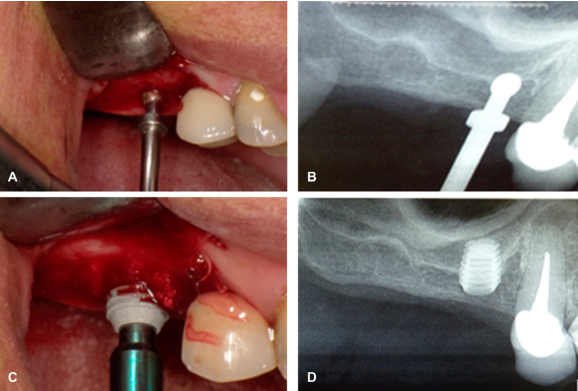

Previa asepsia y antisepsia del área quirúrgica a intervenir, se realizó incisión intrasulcular respetando las papilas de los dientes 14 y 13, con extensión crestal distal sobre el reborde alveolar, preparando colgajo a espesor total permitiendo visión del campo quirúrgico y a continuación se empleó el kit STRAUSS & CO® (Figura 2), el cual permite osteotomía conservadora con tope de profundización, controlando de esta manera el ingreso a reparos anatómicos como el piso del seno maxilar. El kit presenta diferentes fresas con partes activas redondas atraumáticas y posibilidad de control mediante topes estables sobre la cresta alveolar a la hora de ingresar a la zona del tejido duro, evitando así accidentes quirúrgicos, como pueden ser la perforación de la membrana de Schneider. Este tipo de técnicas conservadoras mediante el uso del kit atraumático permiten realizar la preparación del lecho quirúrgico, controlando la perforación del lugar de trabajo de una manera más precisa y rápida (Figura 3A-B). Se empleó una fresa que controla la profundidad de ingreso a 5 mm; posteriormente se utilizaron fresas quirúrgicas mecánicas a 50 RPM sin irrigación para la preparación del lecho quirúrgico e ingreso transalveolar de biomaterial beta fosfato tricálcico, mediante osteotomos manuales que posibilitaron el desplazamiento del piso del seno maxilar y la membrana de Schneider, favoreciendo el aumento de la longitud en la nueva altura ósea obtenida.

Figura 3 Procedimiento quirúrgico. A. Preparación del lecho quirúrgico. B Radiografía digital de control de la preparación del lecho quirúrgico. C. Colocación del implante corto. D. Radiografía digital final con el implante corto, sin perforar el seno maxilar.

Una vez preparado el lecho quirúrgico y habiendo aumentado la altura ósea ideal, se procedió a la colocación inmediata del implante corto con dimensiones de 4.5 x 6.0 mm obteniendo estabilidad y fijación primaria con el fresado mecánico ideal; siguiendo el protocolo del fabricante del implante dental, finalmente se procedió al cierre de los tejidos blandos, con la técnica de sutura continua, sin ninguna complicación quirúrgica (Figura 3C).

Después de tres meses de la colocación del implante, se realizaron controles clínicos y radiografías diagnósticas que constataron una excelente oseointegración, excelente capacidad de retención, sin presencia de lesiones en la zona quirúrgica intervenida alrededor del implante, adaptabilidad ideal, sin perforación del piso del seno maxilar, ni de la membrana de Schneider. En una segunda fase quirúrgica se verificó el implante como estable, sin movilidad y tejidos con buena salud, corroborando la alta tasa de éxito de esta técnica conservadora mínimamente invasiva (Figura 3D).